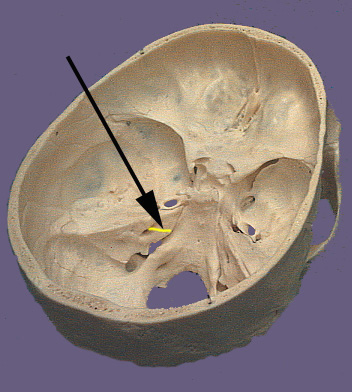

The facial nerve is mixed nerve containing both sensory and motor components. The nerve emanates from the brain stem at the ventral part of the pontomedullary junction. The nerve enters the internal auditory meatus where the sensory part of the nerve forms the geniculate ganglion. In the internal auditory meatus is where the greater petrosal nerve branches from the facial nerve. The facial nerve continues in the facial canal where the chorda tympani branches from it the facial nerve leaves the skull via the styolomastoid foramen. The chorda tympani passes through the petrotympanic fissure before entering the infratemporal fossae. The main body of the facial nerve is somatomotor and supplies the muscles of facial expression. The somatomotor component originates from neurons in the facial motor nucleus located in the ventral pons. The visceral motor or autonomic (parasympathetic) part of the facial nerve is carried by the greater petrosal nerve. The greater petrosal nerve leaves the internal auditory meatus via the hiatus of the greater petrosal nerve which is found on the anterior surface of the petrous part of the temporal bone in the middle cranial fossa. The greater petrosal nerve passes forward across the foramen lacerum where it is joined by the deep petrosal nerve (sympathetic from superior cervical ganglion). Together these two nerves enter the pterygoid canal as the nerve of the pterygoid canal. The greater petrosal nerve exits the canal with the deep petrosal nerve and synapses in the pterygopalatine ganglion in the pterygopalatine fossa. The ganglion then gives of nerve branches which supply the lacrimal gland and the mucous secreting glands of the nasal and oral cavities. The other parasympathetic part of the facial nerve travel with the chorda tympani which joins the lingual nerve in the infratemporal fossa. They travel with lingual nerve prior to synapsing in the submandibular ganglion which is located in the lateral floor of the oral cavity. The submandibular ganglion originates nerve fibers that innervate the submandibular and sublingual glands. The visceral motor components of the facial nerve originate in the lacrimal or superior salivatory nucleus. The nerve fibers exit the brainstem via the nervus intermedius. (The nervus intermedius is so called because of its intermediate location between the eighth cranial nerve and the somatomotor part of the facial nerve just prior to entering the brain). There are two sensory (special and general) components of facial nerve both of which originate from cell bodies in the geniculate ganglion. The special sensory component carries information from the taste buds in the tongue and travel in the chorda tympani. The general sensory component conducts sensation from skin in the external auditory meatus, a small area behind the ear, and external surface of the tympanic membrane. These sensory components are connected with cells in the geniculate ganglion. Both the general and visceral sensory components travel into the brain with nervus intermedius part of the facial nerve. The general sensory component enters the brainstem and eventually synapses in the spinal part of trigeminal nucleus. The special sensory or taste fibers enter the brainstem and terminate in the gustatory nucleus which is a rostral part of the nucleus of the solitary tract.